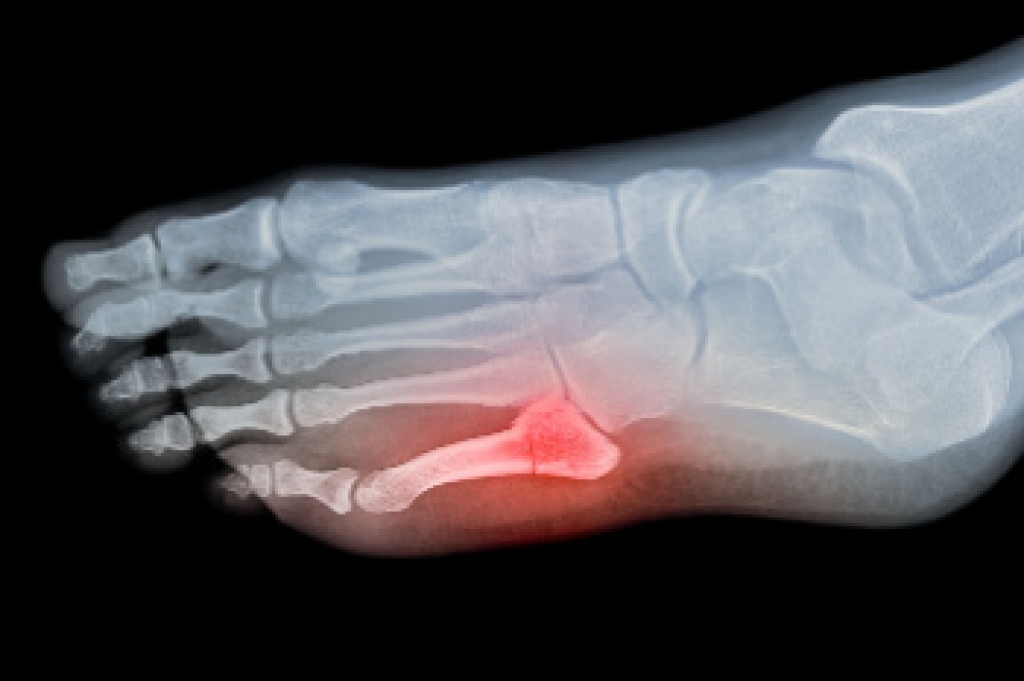

A broken toe is a fracture of one or more of the small bones in the toe, often resulting from sudden trauma. Common causes include a heavy object falling on the foot, or forceful stubbing against furniture or hard surfaces. Symptoms usually involve pain, swelling, bruising, and difficulty walking. Discolored toenails may appear when bleeding occurs beneath the nail. Diagnosis is typically made through a physical exam and imaging, such as X-rays, to confirm the fracture and its severity. Risk factors include sports activities, poor footwear protection, and balance issues. If you have symptoms of a broken toe, it is suggested that you promptly consult a podiatrist who can provide an accurate diagnosis, stabilize the toe, manage pain, and guide proper healing.

A broken toe occurs when one or more of the toe bones of the foot are broken after an injury. Injuries such as stubbing your toe or dropping a heavy object on it may cause a toe fracture.